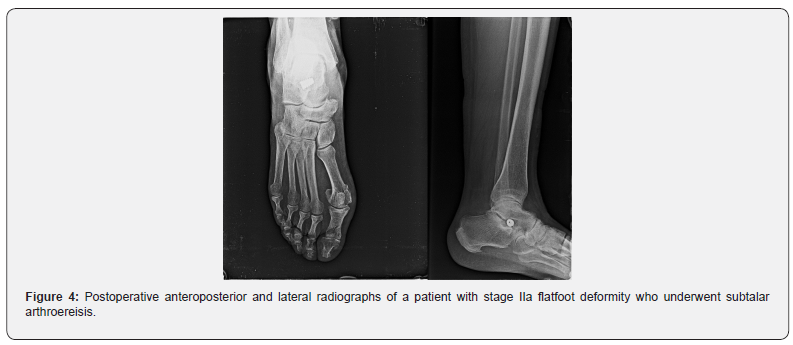

Subtalar arthroereisis has a greater potential of hindfoot valgus correction than calcaneal osteotomy providing a 3-dimensional correction of the flatfoot deformity by repositioning the talus in its physiologic position [20] (Figure 3). Compared with medial displacement calcaneal osteotomy [21], subtalar arthroereisis (Figure 4) it is easy, quick to perform, and less invasive procedure with no risk of nonunion or malunion, no risk of damaging medial neurovascular structures, and it requires less immobilization time and shorter recovery time. There are also disadvantages among which we can mention: limits subtalar joint mobility, the sinus tarsi level pain rate is relatively high (10%–40% of patients) which may require implant removal [22]. Calcaneal osteotomy and subtalar arthroereisis can be performed combined on the same patient to gain more heel valgus correction [19].